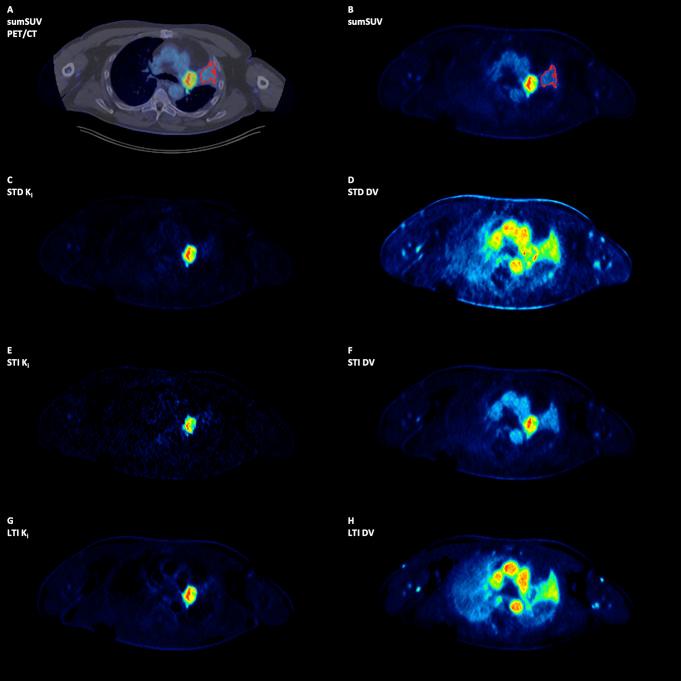

50 oncological patients with 346 tumor lesions were enrolled in the study. All patients underwent [F]FDG PET/CT (skull to upper thigh). Here, the Image-Derived-Input-Function) (IDIF) from the descending aorta was used as the exclusive input function. Four sets of images have been reviewed visually and evaluated quantitatively using the target-to-background (TBR) and contrast-to-noise ratio (CNR): short-time (30 min)-direct (STD) Patlak K, short-time (30 min)-indirect (STI) Patlak K, long-time (59.25 min)-indirect (LTI) Patlak K, and 50-60 min SUV (sumSUV). VOI-based 2TCM was used for the evaluation of tumor lesions and normal tissues and compared with the results of Patlak model.

No significant differences were observed between the four approaches regarding the number of tumor lesions. However, we found three discordant results: a true positive liver lesion in all Patlak K images, a false positive liver lesion delineated only in LTI K which was a hemangioma according to MRI and a true negative example in a patient with an atelectasis next to a lung tumor. STD, STI and LTI K images had superior TBR in comparison with sumSUV images (2.9-, 3.3- and 4.3-fold higher respectively). TBR of LTI K were significantly higher than STD K. VOI-based k showed a 21-fold higher TBR than sumSUV. Parameters of different models vary in their differential capability between tumor lesions and normal tissue like Patlak K which was better in normal lung and 2TCM k which was better in normal liver. 2TCM K revealed the highest correlation (r = 0.95) with the LTI Patlak K in tumor lesions group and demonstrated the highest correlation with the STD Patlak K in all tissues group and normal tissues group (r = 0.93 and r = 0.74 respectively).

50例患有346个肿瘤病变的肿瘤患者纳入本研究。所有患者均接受了[F]FDG PET/CT(从头颅到大腿上部)检查。在此,将降主动脉的图像衍生输入函数(IDIF)用作唯一的输入函数。四组图像已进行视觉检查,并使用靶本比(TBR)和对比噪声比(CNR)进行定量评估:短时间(30分钟)直接(STD)Patlak K、短时间(30分钟)间接(STI)Patlak K、长时间(59.25分钟)间接(LTI)Patlak K以及50-60分钟SUV(总SUV)。基于感兴趣区(VOI)的2TCM用于评估肿瘤病变和正常组织,并与Patlak模型的结果进行比较。

在肿瘤病变数量方面,四种方法之间未观察到显著差异。然而,我们发现了三个不一致的结果:所有Patlak K图像中一个真正的肝脏阳性病变、仅在LTI K中勾勒出的一个假阳性肝脏病变(根据MRI为血管瘤)以及一名肺肿瘤旁有肺不张患者中的一个真正阴性病例。与总SUV图像相比,STD、STI和LTI K图像具有更高的TBR(分别高出2.9倍、3.3倍和4.3倍)。LTI K的TBR显著高于STD K。基于VOI的k显示其TBR比总SUV高21倍。不同模型的参数在区分肿瘤病变和正常组织的能力方面有所不同,如Patlak K在正常肺组织中表现更好,而2TCM k在正常肝脏组织中表现更好。2TCM K在肿瘤病变组中与LTI Patlak K的相关性最高(r = 0.95),在所有组织组和正常组织组中与STD Patlak K的相关性最高(分别为r = 0.93和r = 0.74)。